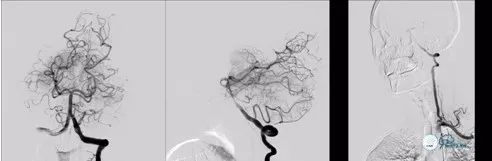

有股动脉穿刺置入6F 70cm血管长鞘至V2段,全身肝素化,置入5F 130cm NV导管至V4段,synchro导丝引导select plus 微导管通过血栓段至左侧大脑后动脉P2段,微导管造影确认真腔后,跨越闭塞段释放solitareAB 6-30取栓支架,等待5分钟,中间导管在支架锚定下引导至基底动脉尖端部,保持负压抽吸,先超选到左侧大脑后动脉P1段进行取栓。

图6

对左侧大脑后动脉取栓后后复查造影提示:左侧大脑后动脉恢复前向血流mTICI3级;右侧大脑后动脉P1远端未见显影。与左侧进行相同操作;synchro导丝引导select plus 微导管通过血栓段至右侧大脑后动脉P2段,微导管造影确认真腔后,跨越闭塞段释放solitareAB 6-30取栓支架,等待5分钟,中间导管在支架锚定下引导至基底动脉尖端部,保持负压抽吸,先超选到右侧大脑后动脉P1段进行取栓。

图7

取栓后复查造影提示:基底动脉级双侧大脑后动脉前向血流mTICI 3级,血管腔内未见血栓级狭窄影像,左侧椎动脉通道未见明显痉挛、夹层等影像。

图8